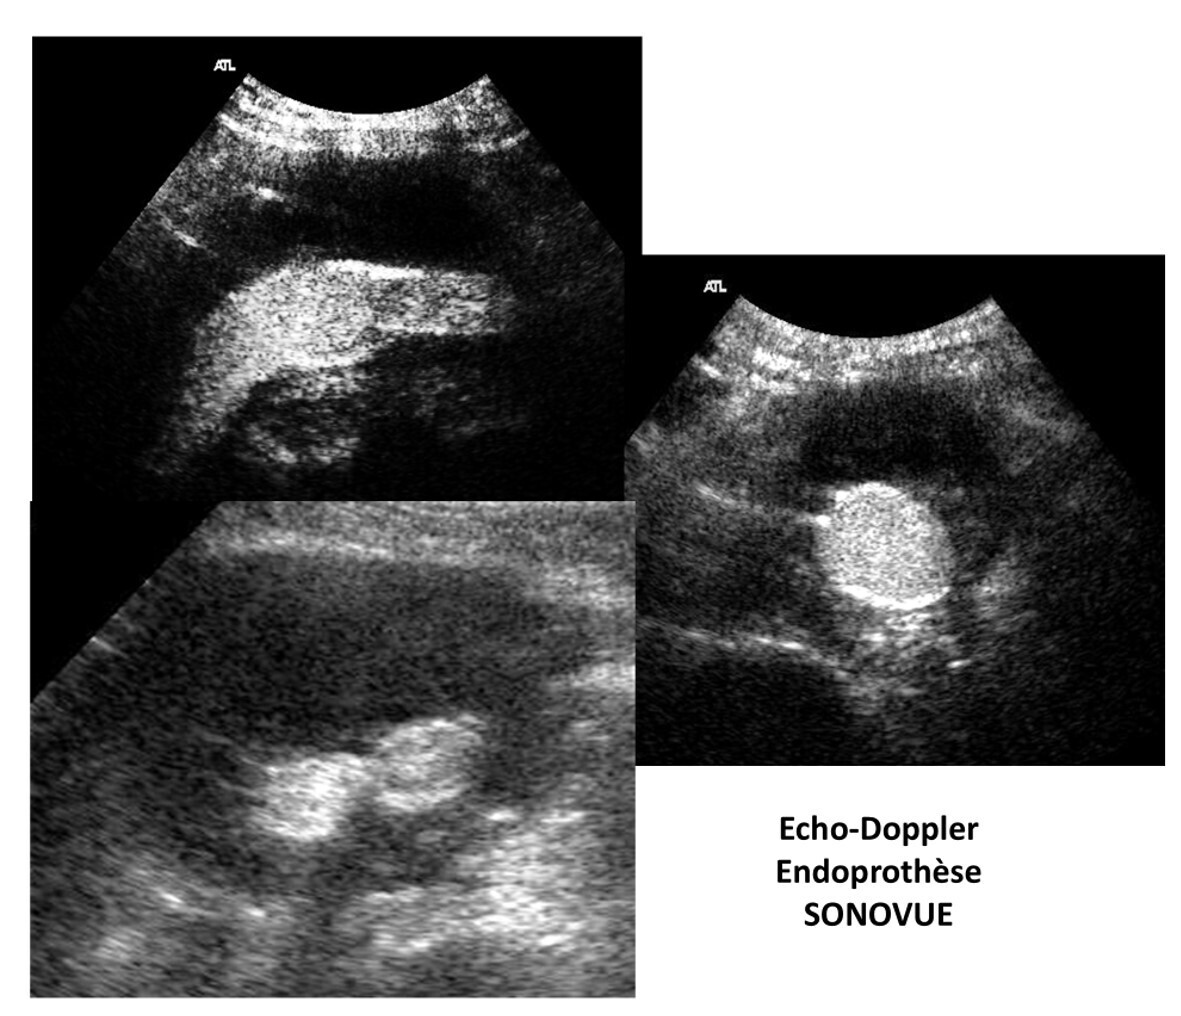

3/ La phase postopératoire : contrôle de l'endoprothèse, mesure du DAP, examen systématique avec injection d'un produit de contraste (SONOVUE) , technique plus précise pour la détection des endofuites. Cet examen avec contraste ne sera pas répété sauf doute sur une endofuite lors de ce suivi.

4/ Suivi de l'endoprothèse : à 6 mois, puis 12 mois puis annuellement ou tous les 6 mois selon le contexte.